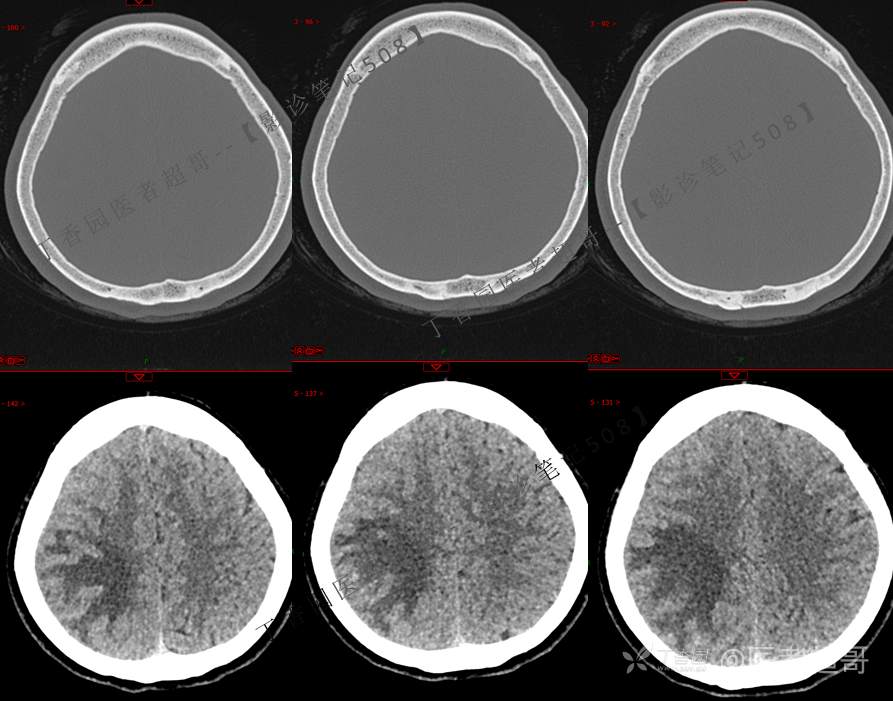

【影诊笔记508】同病异影,个人感觉有难度,欢迎分析,领丁当!有详细术程及病理!

主 诉:突发一过性意识不清伴肢体抽搐5天余。

现病史:患者5天余前无明显原因及诱因出现一过性意识不清,伴肢体抽搐,持续约2-3分钟,后意识逐渐恢复,无明显头痛头晕,无恶心呕吐,无肢体抽搐,无呼吸困难,无二便失禁,后就诊于当地医院,行颅脑CT示“颅内占位性病变”,予以药物对症治疗,具体不详,门诊以“颅内占位性病变”,收入我科。患者自发病以来,未进饮食,近期体重无明显变化。